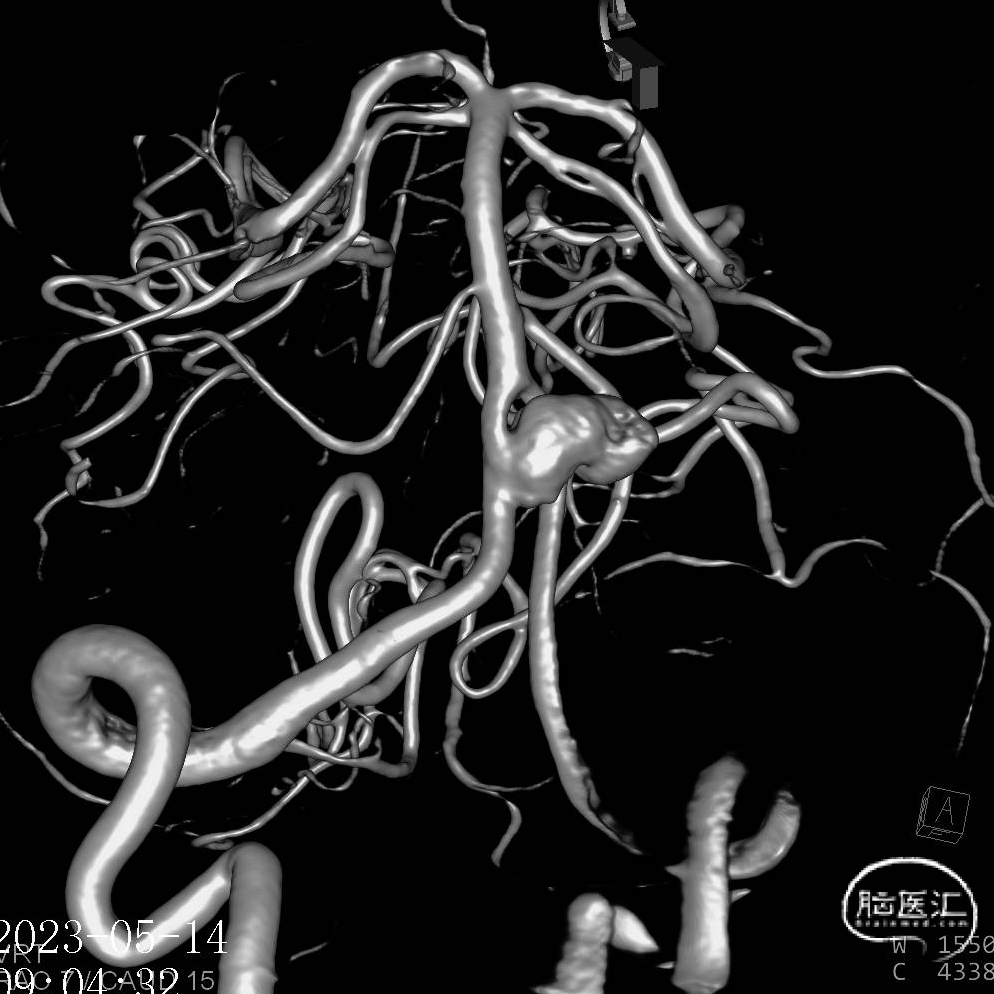

6.右侧颈内动脉C7段、左侧大脑中动脉M1段、基底动脉末端动脉瘤

动脉瘤一:基底动脉末端动脉瘤

(小脑上动脉瘤,侧壁)

动脉瘤一:基底动脉末端动脉瘤,由左侧大脑后动脉与左侧小脑上动脉瘤夹角处动脉瘤形成且为不规则状;瘤体上有子囊形成,左侧小脑上动脉从近心端瘤颈处动脉瘤瘤体上发出,动脉瘤与载瘤动脉近直角。

经测量可得动脉瘤宽度平均值为8.88mm,动脉瘤最小高度为7.71mm,瘤颈约为4.03mm。参考尺寸选择表,选择WEB™ SL 10*5,VIA™ 33微导管。